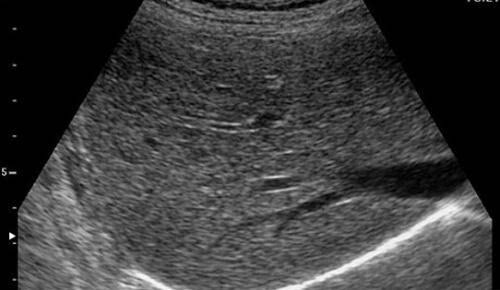

超声表现:

1.肝实质回声细密增强,呈云雾状,后方回声衰减。

2.肝内管道结构显示欠清。

3.肝肾对比阳性,正常情况下肝脏回声略高于肾实质回声,脂肪肝时肝脏回声明显增强。

4.肝脏增大,形态饱满,边缘变钝。

脂肪肝的分度:

根据肝脏回声,肝内管道及膈肌显示情况可对脂肪肝进行分度。

轻度:肝回声增强,后方回声衰减不明显,肝内管道结构显示正常。

中度:肝回声明显增强,后方回声衰减,肝内管道结构显示欠清晰。

重度:后方回声衰减明显,后方肝组织显示不清,膈肌显示不清。